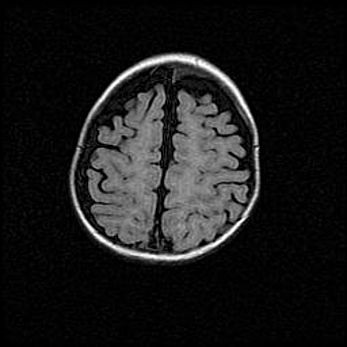

Церебральная ишемия II.

Возраст: 5 дней

Вес: 3400 г

Пол: женский

Окружность головы: 35 см

Срок гестации: 39 недель

Церебральная ишемия – это заболевание, характеризующееся недостаточностью (гипоксией) либо полным прекращением (аноксией) снабжения мозга кислородом по причине закупорки одного или нескольких сосудов. Это приводит к  что метаболическим расстройствам различной степени тяжести в тканях головного мозга, развитию коагуляционных некрозов и гибели нейронов.